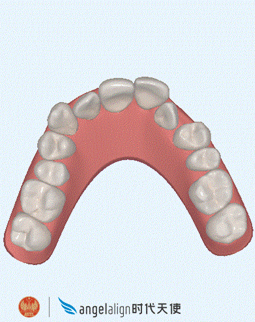

主任给我做了矫牙方案设计,这是3D隐形矫牙动画预览, 显示牙齿不齐的动画,提前预知矫牙后效果,每一步都可以看到矫牙后的牙齿形态,真的很安全放心。让我矫牙过程中一点都不担心会不会矫正会出现其他问题。